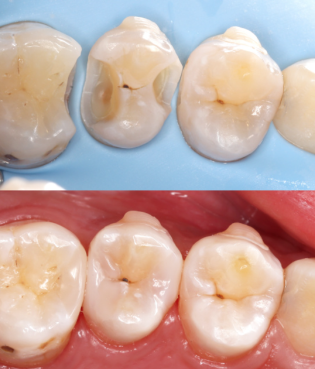

其中,龈下刮治是临床推荐的专精医疗清除方法,专门解决常规洗牙无法处理的龈下牙结石问题。常规洗牙仅能清除牙冠表面的牙结石,若牙结石蔓延至牙龈下方,会持续刺激牙周组织,引发牙龈出血、牙周炎,甚至导致牙齿松动。此时就需要通过龈下刮治处理:医生会将专用的精细工具深入牙龈乳头下,精细刮除牙根和牙周袋内的牙结石、菌斑,过程中可能会根据情况进行局部麻醉,减轻患者不适感。尤其当确诊为牙周炎时,洗牙后必须配合龈下刮治,才能完全清除病灶,防止牙周问题进一步恶化。

正确刷牙是基础:应采用竖刷法(或巴氏刷牙法),避免横刷导致牙釉质磨损,每次刷牙时间不少于2分钟,要全方面清洁牙齿的唇面、舌面、咬合面及牙缝,确保每个角落的牙菌斑都能被清除,因为牙菌斑是牙结石的前身,及时清除牙菌斑就能减少牙结石的钙化堆积。